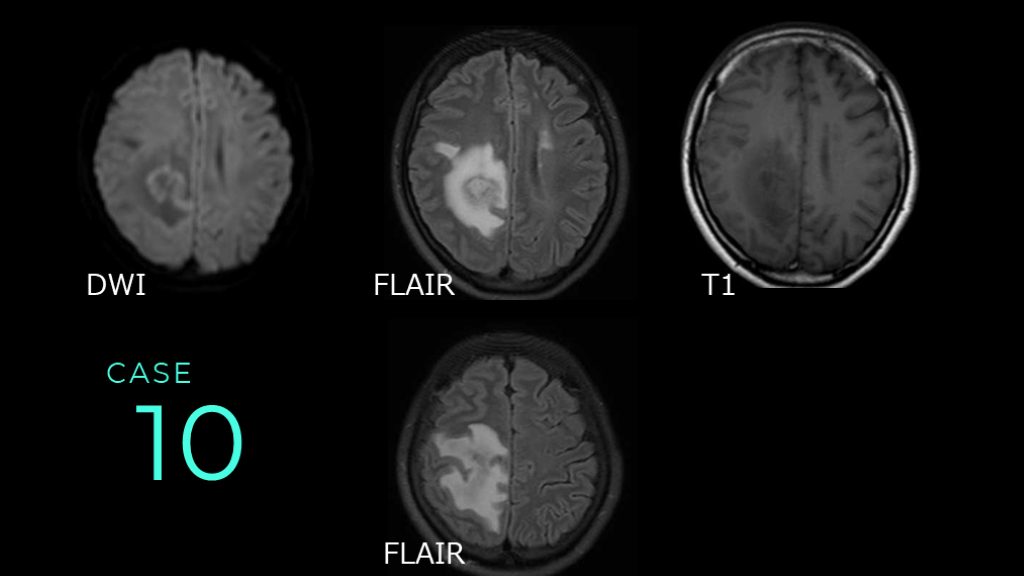

10 CASE DWI FLAIR T1 FLAIR

10 CASE DWIでは右側頭頂部に淡いLOWの病変あり。FLAIRでは内部にややHIGHの腫瘤性病変があり、その周囲の白質に高信号病変がある。同病変はT1ではLOWである。 DWI FLAIR T1

10 CASE コメント:脳腫瘍症例。Mass effectといって、FLAIR HIGHで見える高信号病変が、腫瘤の周囲に認められる。